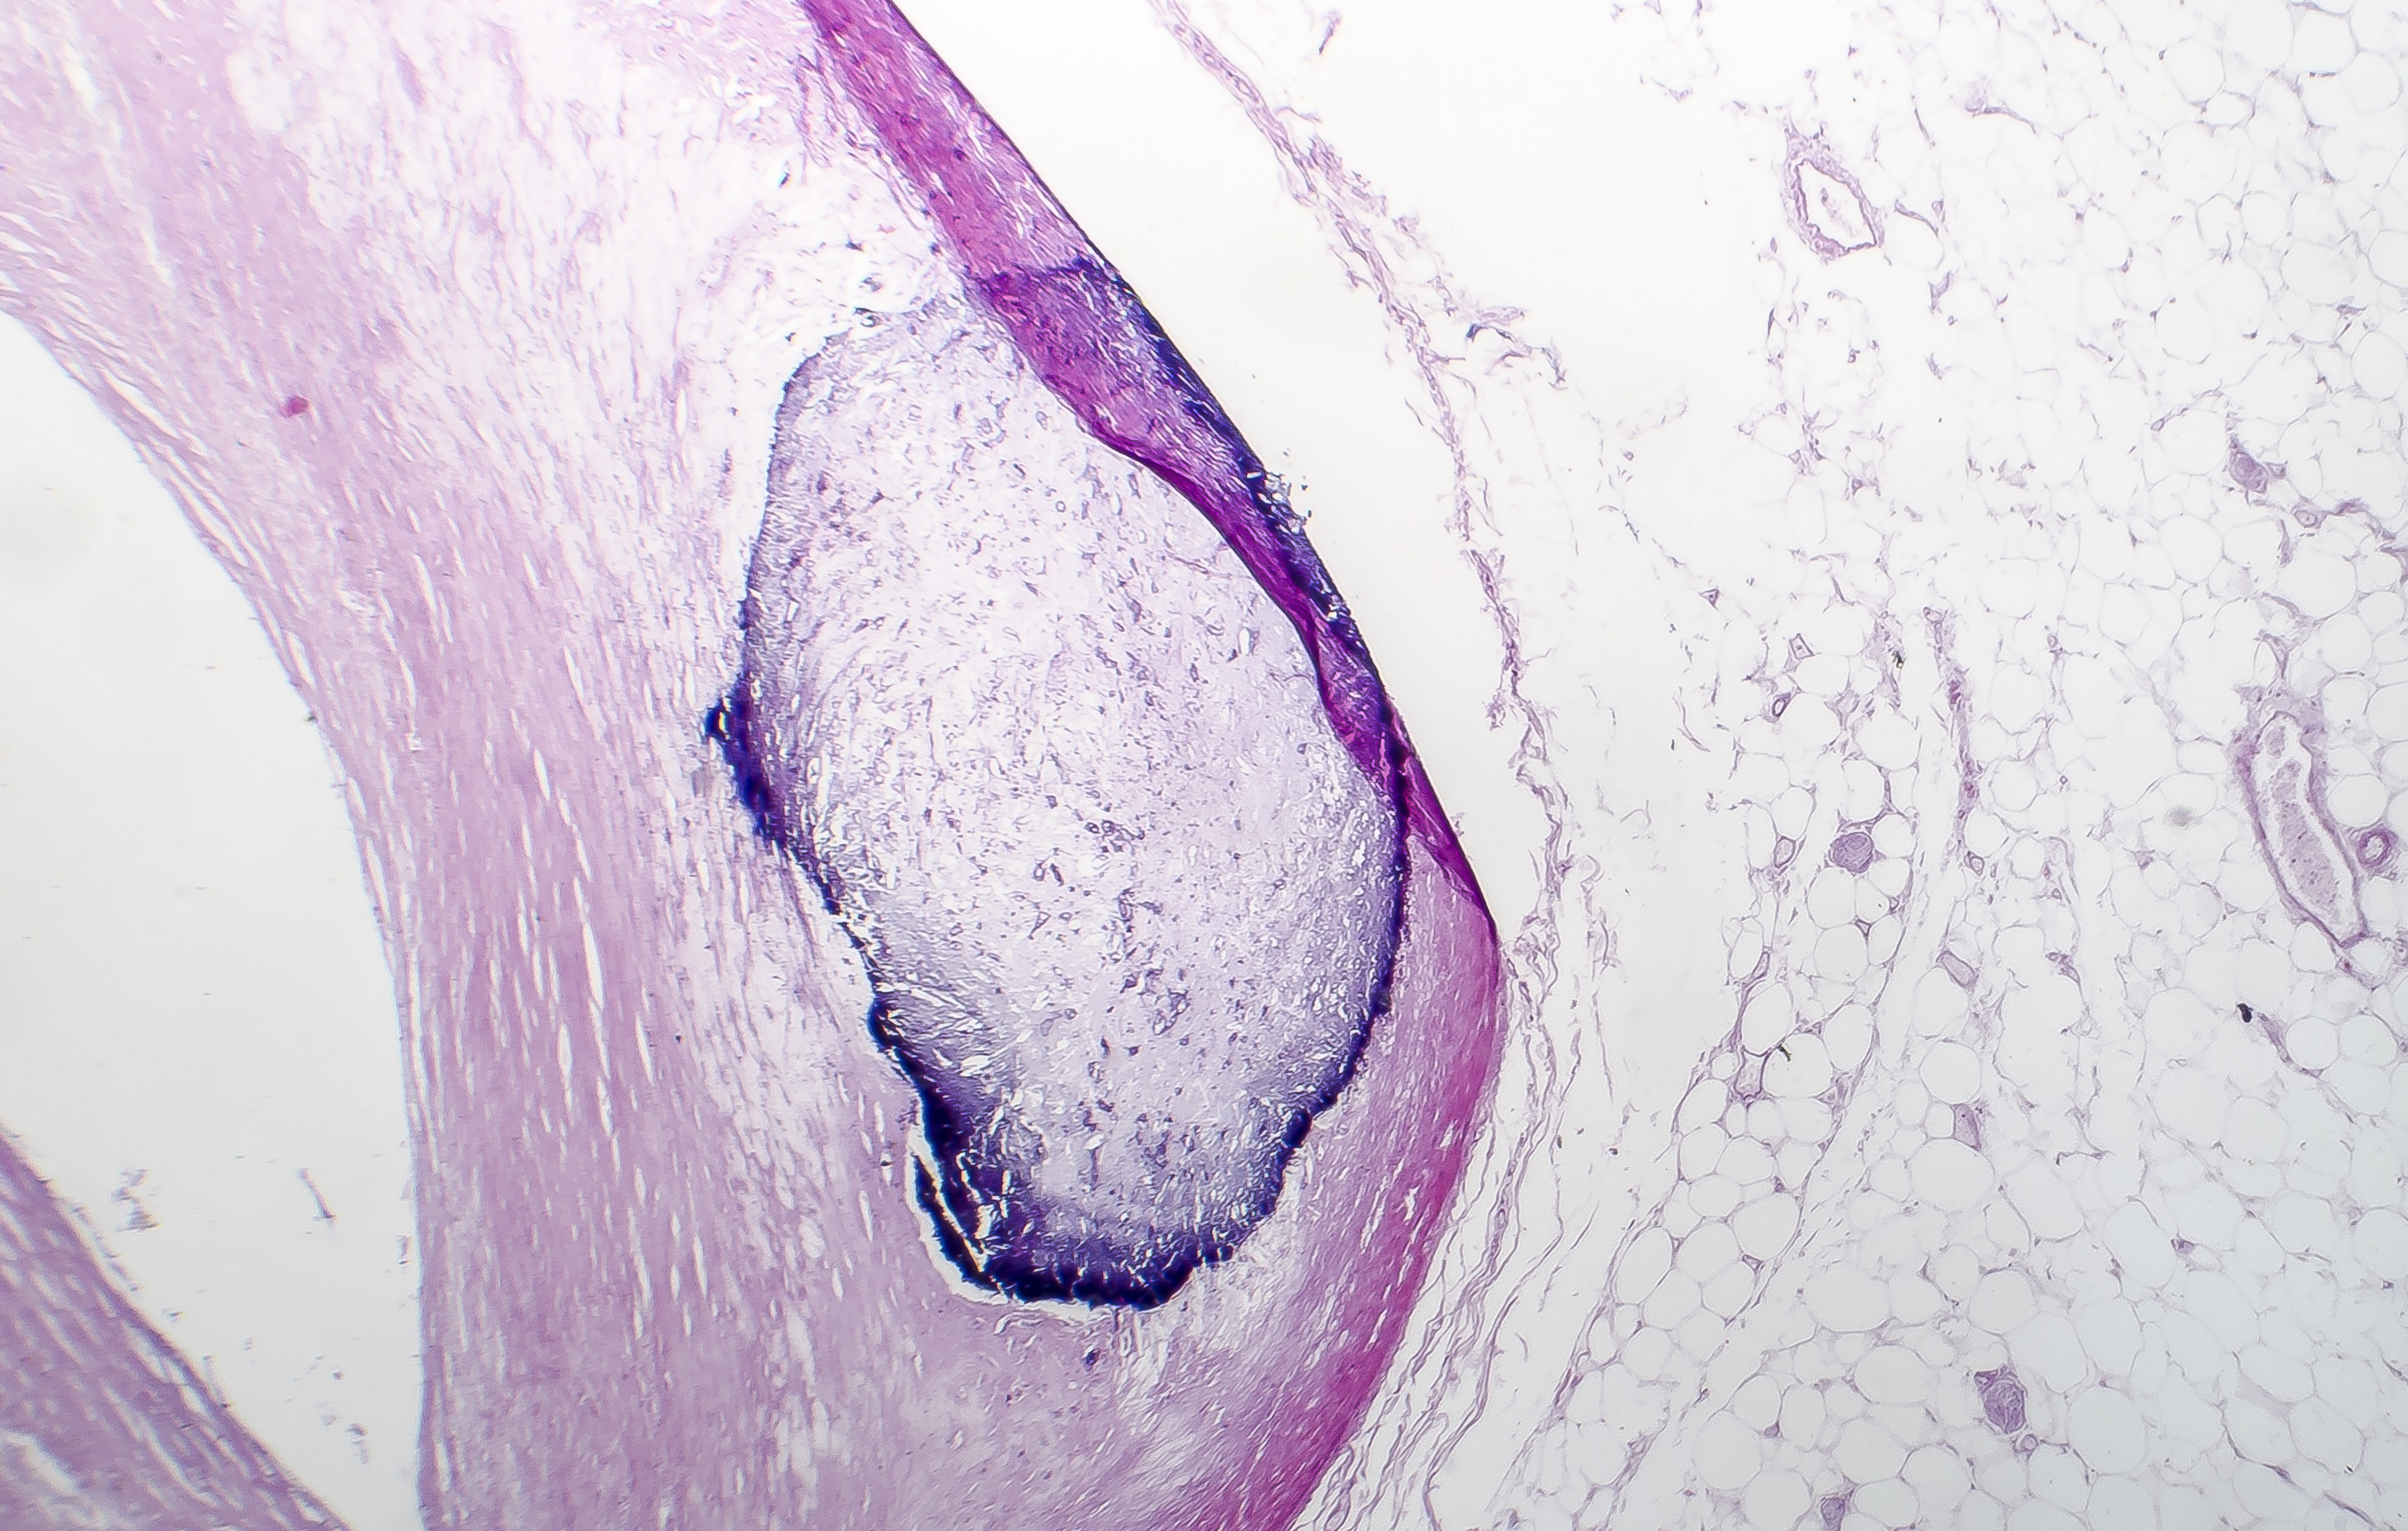

The calcification process often begins with damage to the inner lining of arteries, known as the endothelium. This damage can be caused by various factors, including high blood pressure, high cholesterol, smoking, and diabetes. As the body attempts to repair this damage, calcium can accumulate in the arterial walls, leading to hardening and narrowing of the blood vessels.

Types of Arterial Calcification

There are two main types of arterial calcification:

- Intimal calcification: Occurs within atherosclerotic plaques

- Medial calcification: Affects the middle layer of the artery wall

Both types can contribute to reduced arterial elasticity and increased cardiovascular risk.